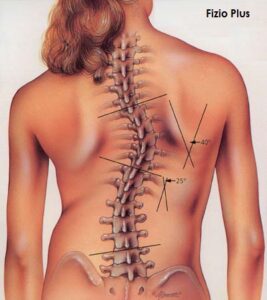

Eshtë një situatë patologjike që përfshin një deviacion lateral dhe rrotullues të shtyllës kurrizore. Nganjëherë rrotullimi përcakton edhe një deformim të kafazit të kraharorit dhe